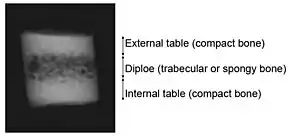

The bones of the skull are in three layers: the hard compact layer of the external table (lamina externa), the diploë (a spongy layer of red bone marrow in the middle, and the compact layer of the inner table (Lamina interna).[25]

Skull thickness is variable, depending on location. Thus the traumatic impact required to cause a fracture depends on the impact site. The skull is thick at the glabella, the external occipital protuberance, the mastoid processes, and the external angular process of the frontal bone. Areas of the skull that are covered with muscle have no underlying diploë formation between the internal and external lamina, which results in thin bone more susceptible to fractures.

Skull fractures occur more easily at the thin squamous temporal and parietal bones, the sphenoid sinus, the foramen magnum (the opening at the base of the skull that the spinal cord passes through), the petrous temporal ridge, and the inner portions of the sphenoid wings at the base of the skull. The middle cranial fossa, a depression at the base of the cranial cavity forms the thinnest part of the skull and is thus the weakest part. This area of the cranial floor is weakened further by the presence of multiple foramina; as a result this section is at higher risk for basilar skull fractures to occur. Other areas more susceptible to fractures are the cribriform plate, the roof of orbits in the anterior cranial fossa, and the areas between the mastoid and dural sinuses in the posterior cranial fossa.[26]